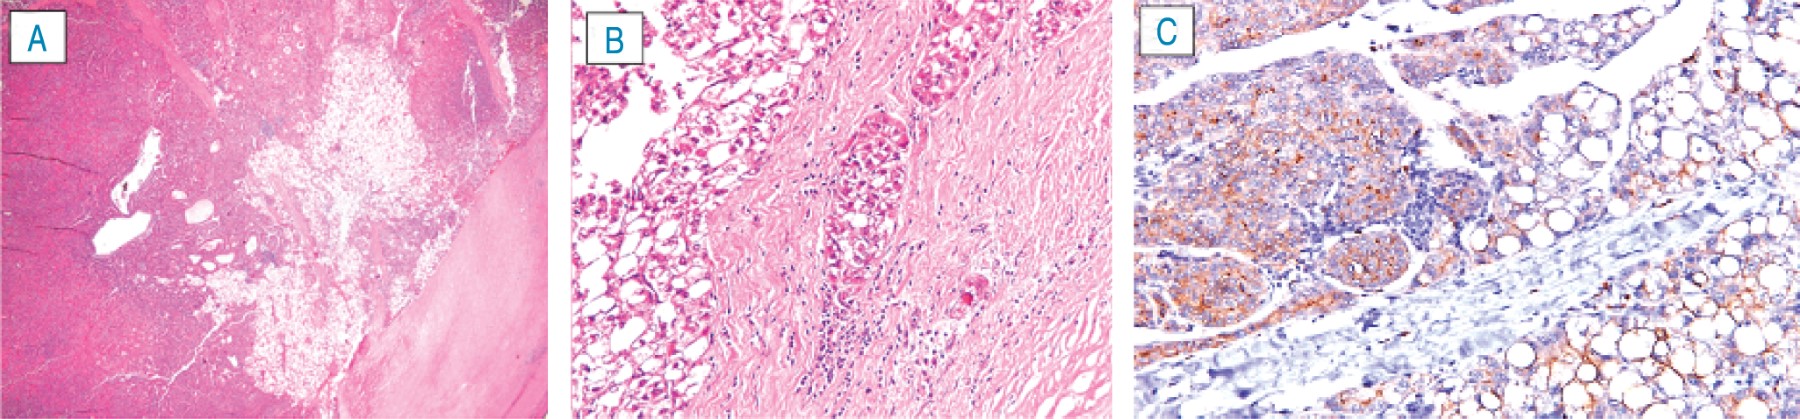

The histopathology report of segment II of the liver concluded a hepatocellular carcinoma with the proliferation of cells arranged in a mixed pattern (trabecular, acinar, and clear cell) with invasion of the capsule (Figure 3) but with free borders, for which clinical oncology was consulted for follow-up and complementary treatment.

Figure 3